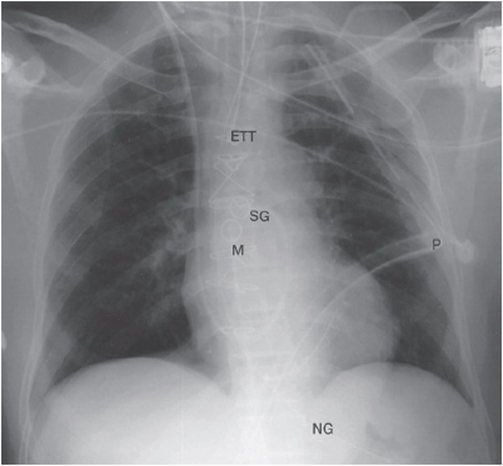

3. ICU patients are almost always imaged supine and are not able to take deep inspirations. Low lung volumes and portable technique significantly impair the ability to evaluate the lung parenchyma. Therefore, the most important function of the ICU chest x-ray is to identify tubes, lines, and drains and assure that they are in the proper positions. Three of the most important items you will use a CXR to assess include endotracheal tubes, esophagogastric tubes (including orogastric and nasogastric tubes), and central venous catheters (see Figure 25-2).

Figure 25-2. Frontal radiograph immediately after coronary artery bypass surgery shows typical lines and tubes encountered in the ICU. Endotracheal tube (ETT), nasogastric tube (NG), Swan-Ganz catheter (SG), mediastinal drain (M), and left pleural drain (P) are present.